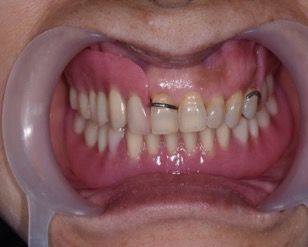

下顎植牙兩顆-林錫奎醫師

下顎植牙兩顆

治療中

安裝後